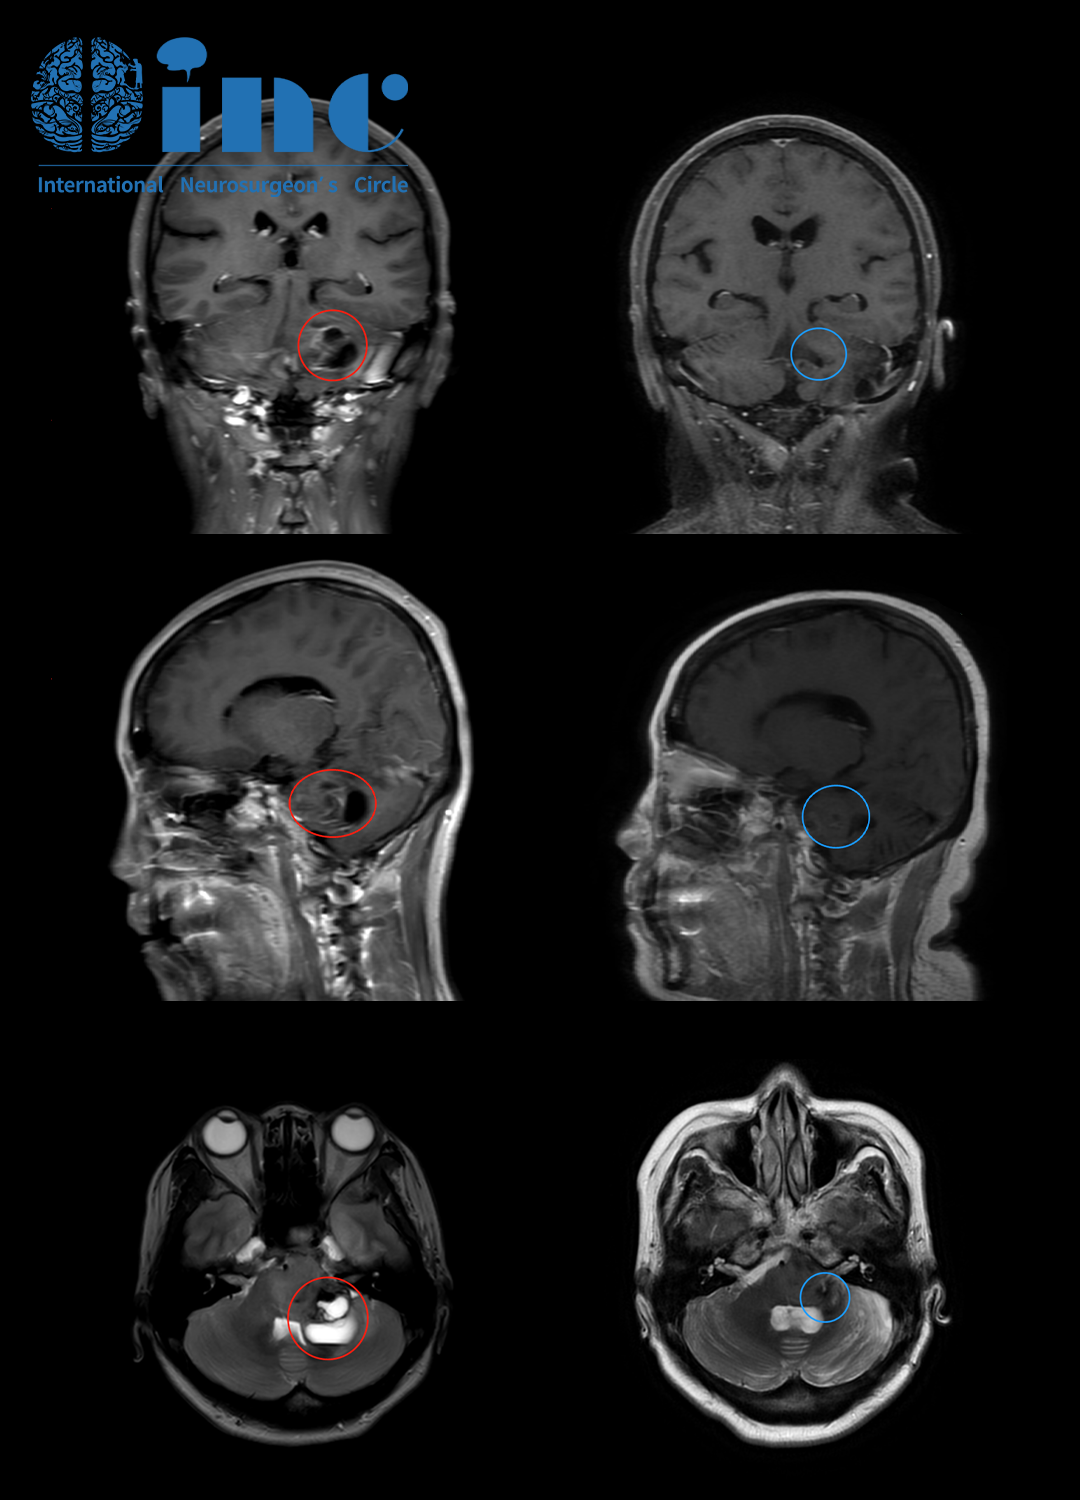

吳女士術(shù)前MRI

吳女士術(shù)前(紅色)術(shù)后(藍(lán)色)MRI對(duì)比